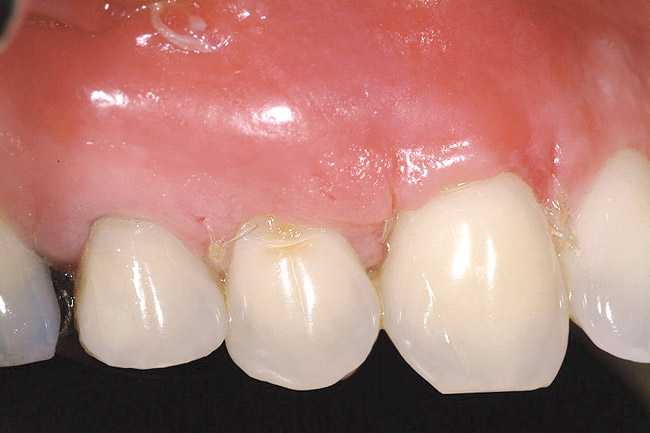

A 54-year-old non-smoking woman presented for correction of deep-wide gingival recession in the maxillary anterior (Figure 1 through Figure 3). The patient’s desires were to correct the gingival recession, balance the heights of contour of the tissues, and possibly undergo esthetic enhancement of the maxillary anterior with veneer restorations.

Figure 3  Case One Pretreatment clinical view, Case 1, maxillary left.

Figure 3

A 27-year-old non-smoking man presented for esthetic enhancement of the left central incisor, which had a pre-existing full-coverage restoration that required replacement (Figure 16). The patient had begun orthodontic treatment in the mandibular arch to correct a minor occlusal imbalance and required coronal repositioning and soft tissue grafting to correct gingival recession at the facial of the right canine, in addition to correction of the free gingival margin at the facial of the left central incisor, which was asymmetrical to the free gingival margin of tooth No. 8. Additionally, the facial gingival tissues were of a thin biotype, which at the facial surface of the left central incisor allowed for the darkened root surface to be visible through the tissue (Figure 16).

Figure 16  Case Two Preoperative clinical view, maxillary left central incisor.

Figure 16